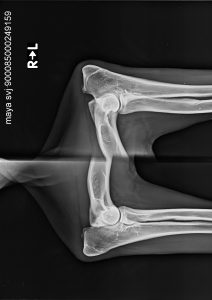

Egészségügyi szűrések